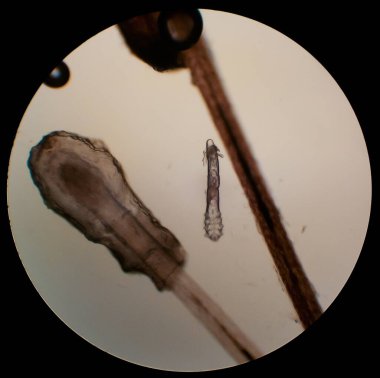

Orta Ürik asit kristal iğne şekli

Eser Sahibi: Chirawan Somsanuk